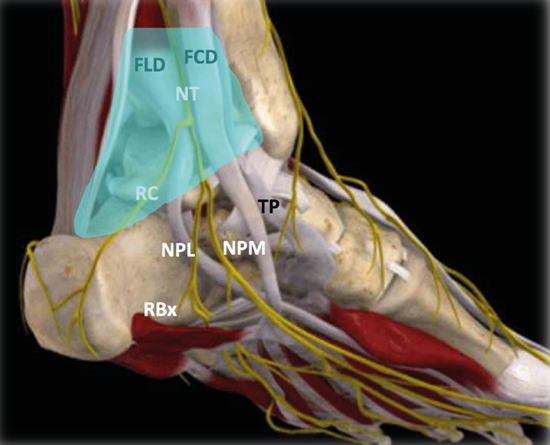

Para realizar la exploración sonográfica, se debe exponer la cara medial del tobillo y el pie. Se ha de comenzar con el examen del nervio tibial en eje corto (plano transverso), situando la sonda en el túnel tibiotalar superior (Figuras 4 y 5)5.

Figura 5. Túnel tibiotalocalcáneo. La porción proximal o túnel tibiotalar superior en azul. Estructuras nerviosas: nervio tibial (NT), rama calcánea (RC), nervio plantar lateral (NPL), nervio plantar medial (NPM), rama de Baxter (RBx). Estructuras musculotendinosas: tibial posterior (TP), flexor largo del primer dedo (FLD) y flexor largo de los dedos (FCD). Imagen modificada de la App Ankle & Foot Pro III.